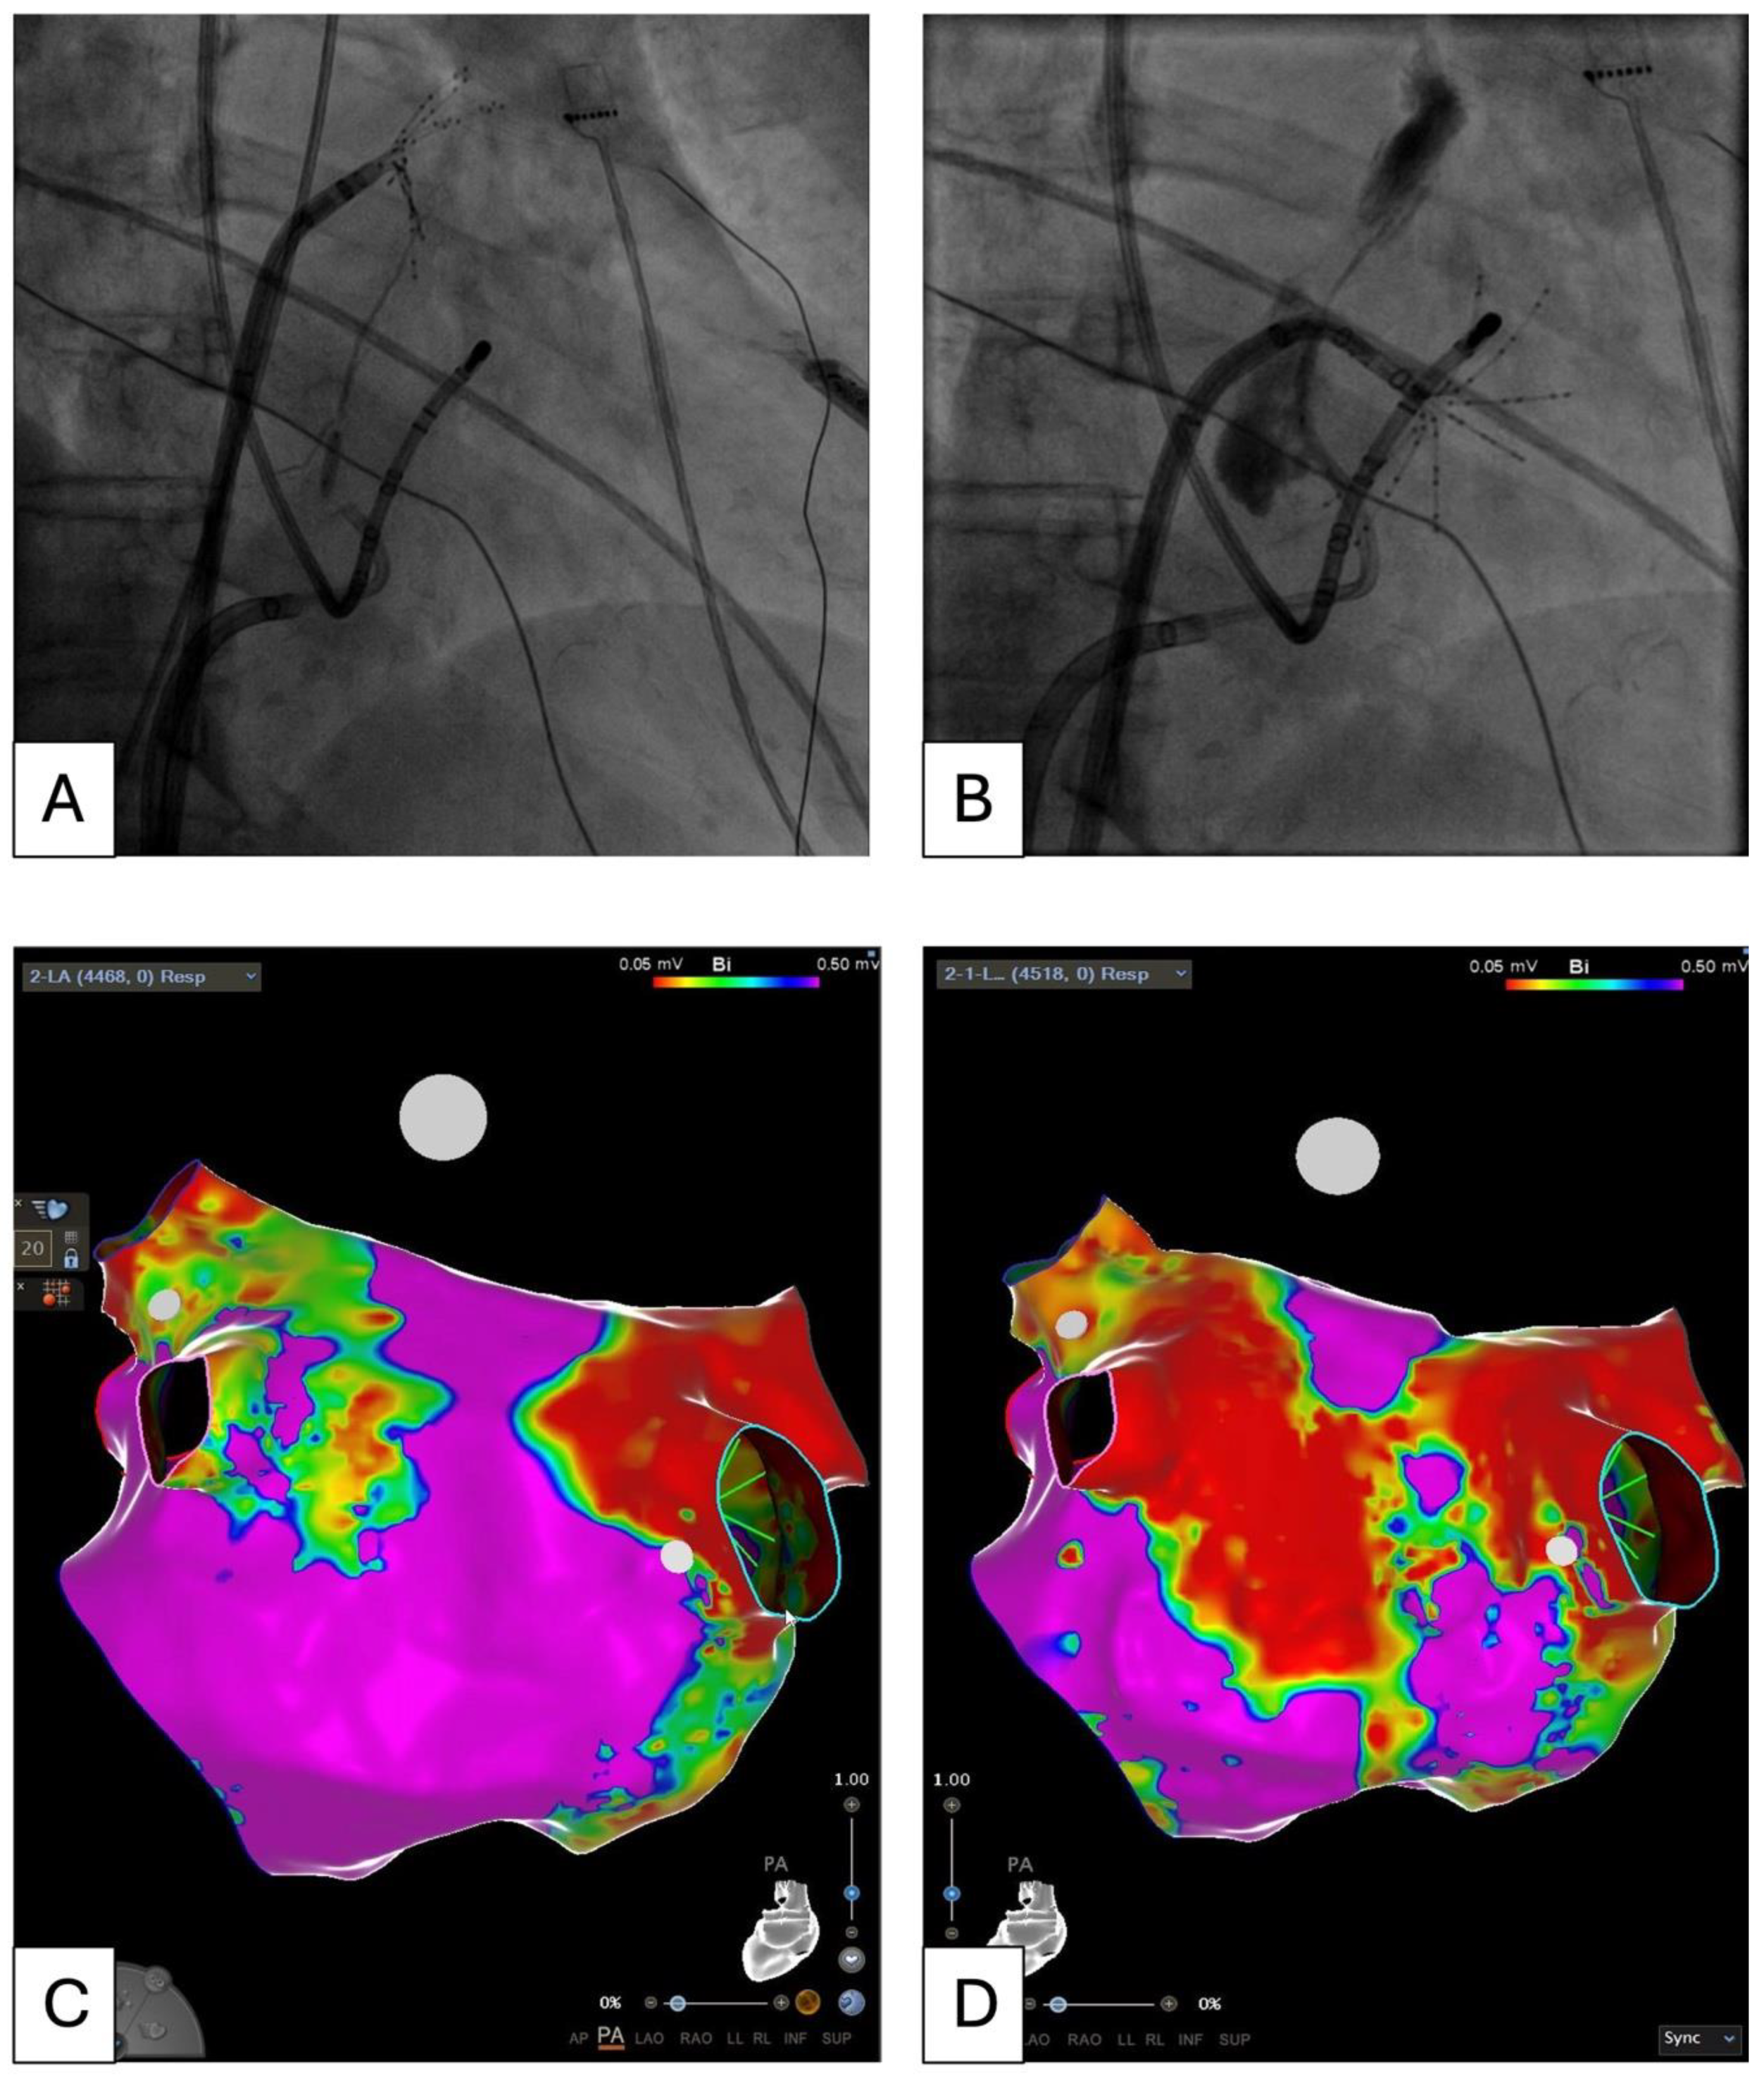

- Rolf, S.; Kircher, S.; Arya, A.; Eitel, C.; Sommer, P.; Richter, S.; Gaspar, T.; Bollmann, A.; Altmann, D.; Piedra, C.; et al. Tailored Atrial Substrate Modification Based on Low-Voltage Areas in Catheter Ablation of Atrial Fibrillation. Circ. Arrhythmia Electrophysiol. 2014, 7, 825–833. [Google Scholar] [CrossRef] [PubMed]

- Li, K.; Xu, C.; Zhu, X.; Wang, X.; Ye, P.; Jiang, W.; Wu, S.; Xu, K.; Li, X.; Wang, Y.; et al. Multi-Centre, Prospective Randomized Comparison of Three Different Substrate Ablation Strategies for Persistent Atrial Fibrillation. Europace 2023, 25, euad090. [Google Scholar] [CrossRef]